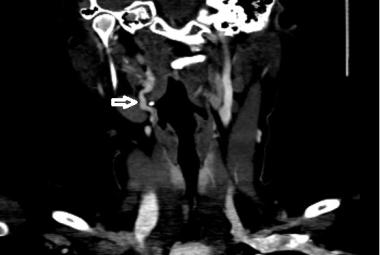

Tracheal dehiscence (white arrow) and surrounding slough just above the tracheostomy tube.

Montgomery T-tube to Bypass Tracheal Dehiscence: UiTM Experience